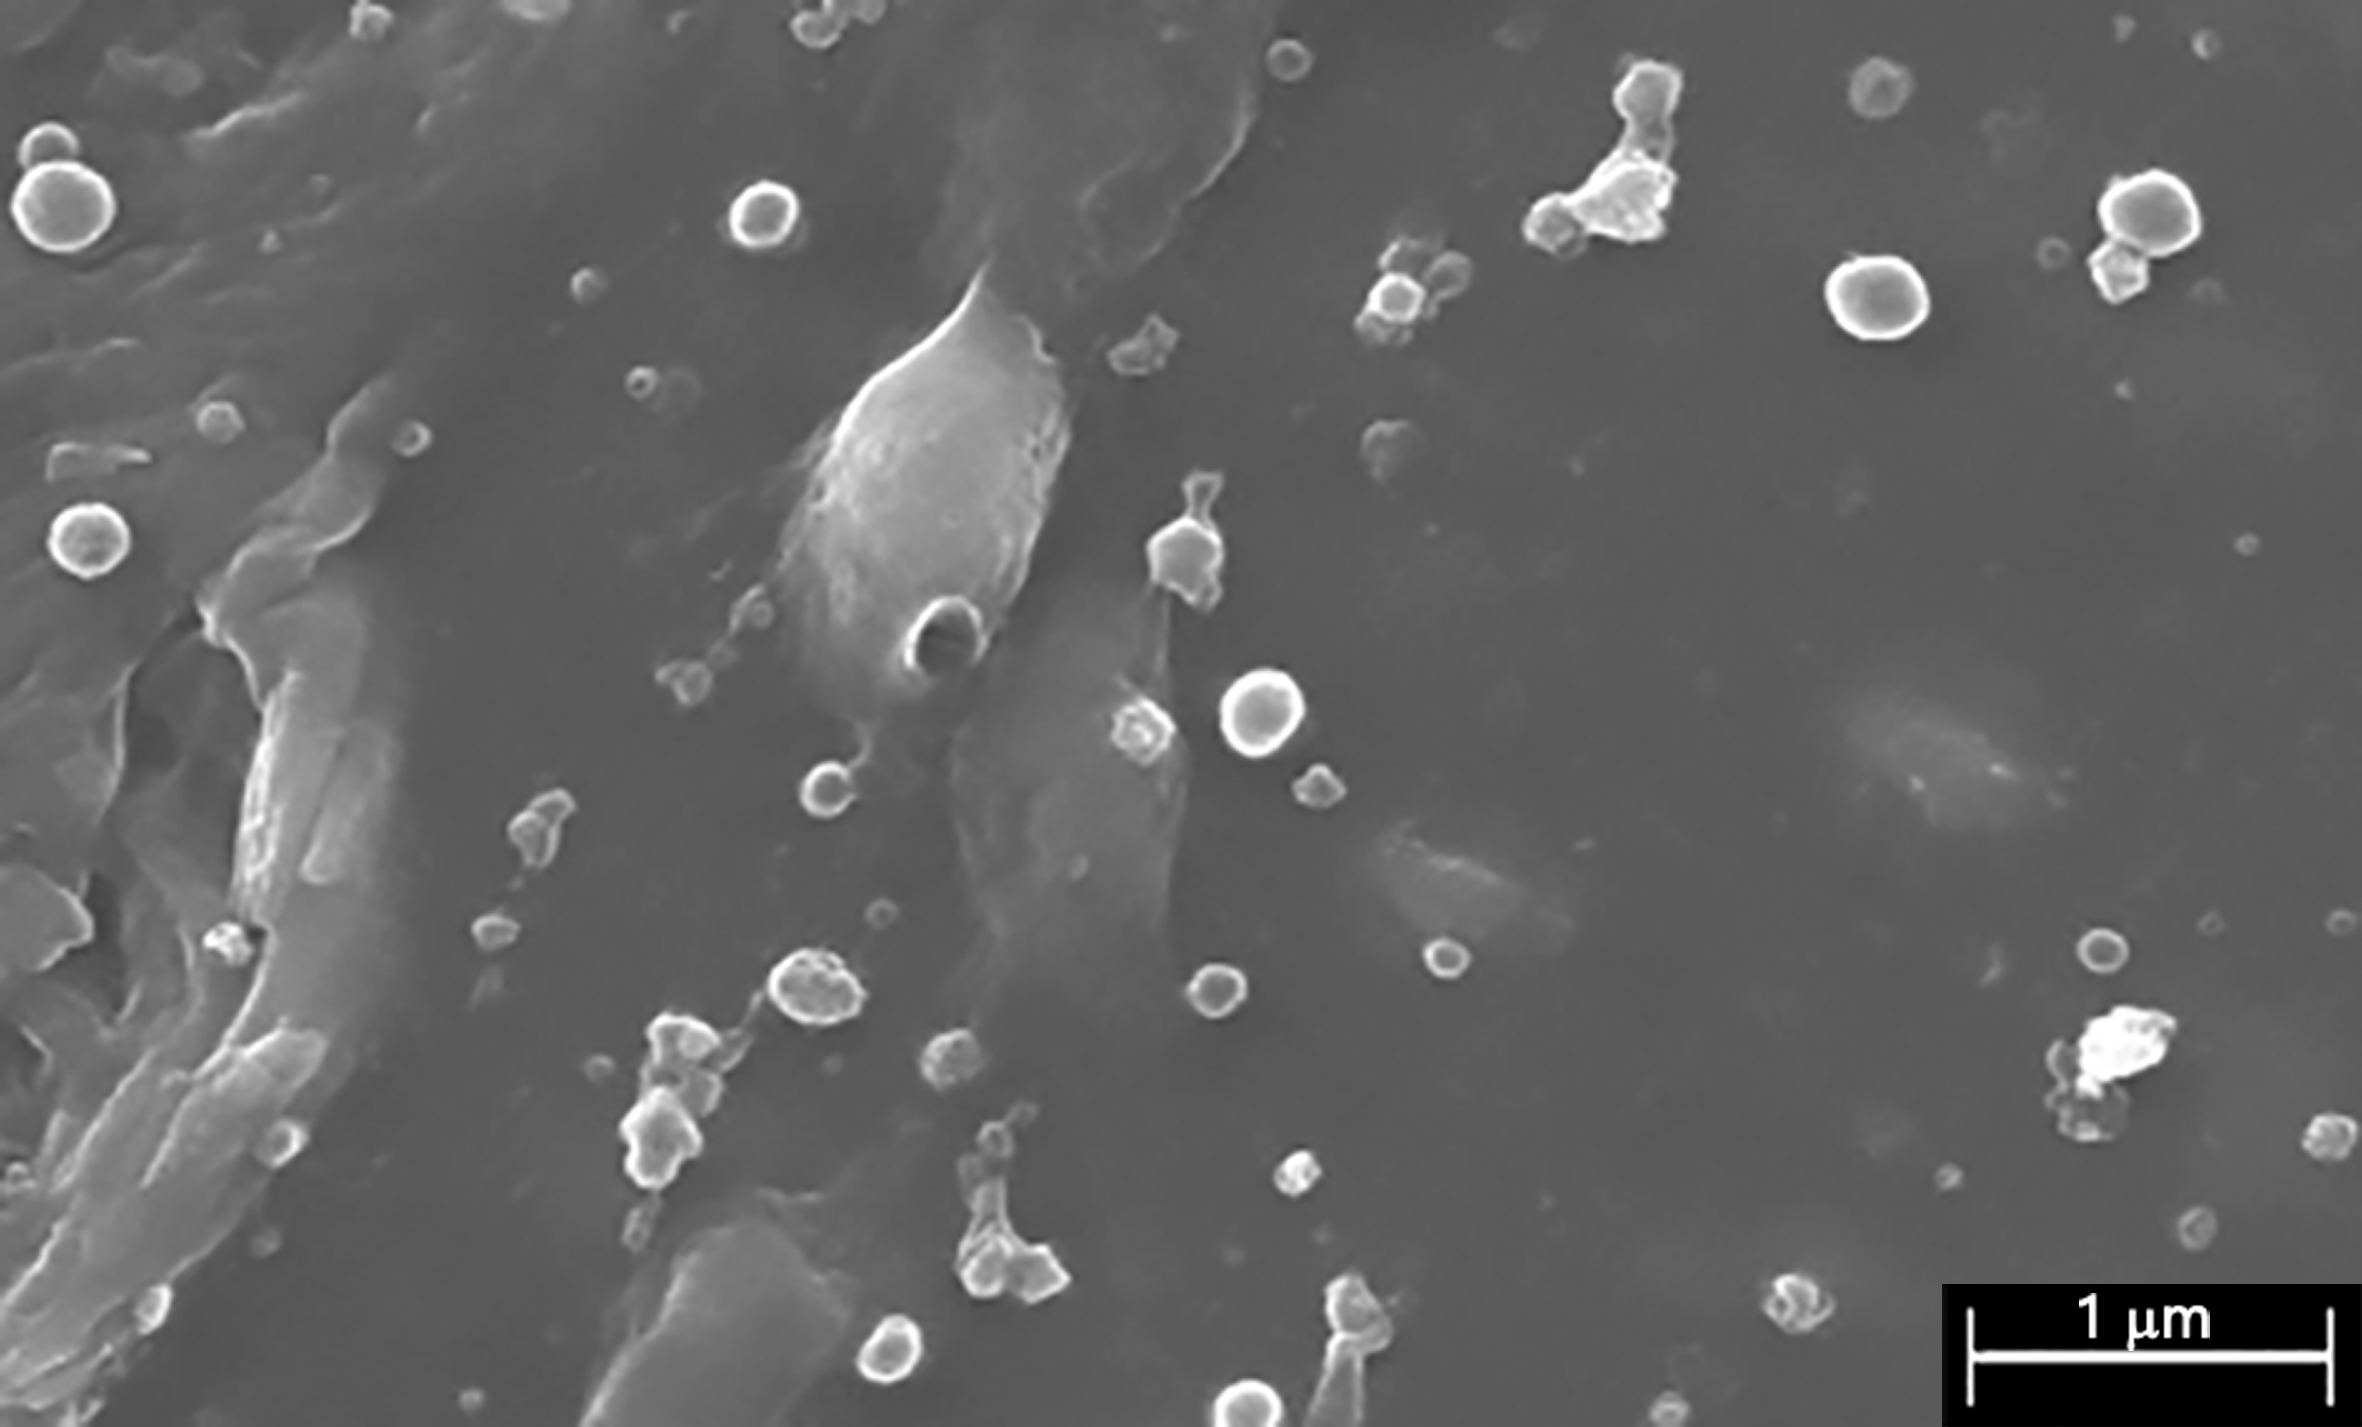

2.4. Visualization of the PLGA-Nanoparticles Loaded Biocomposites

3.1. Bioactive Polymeric Film